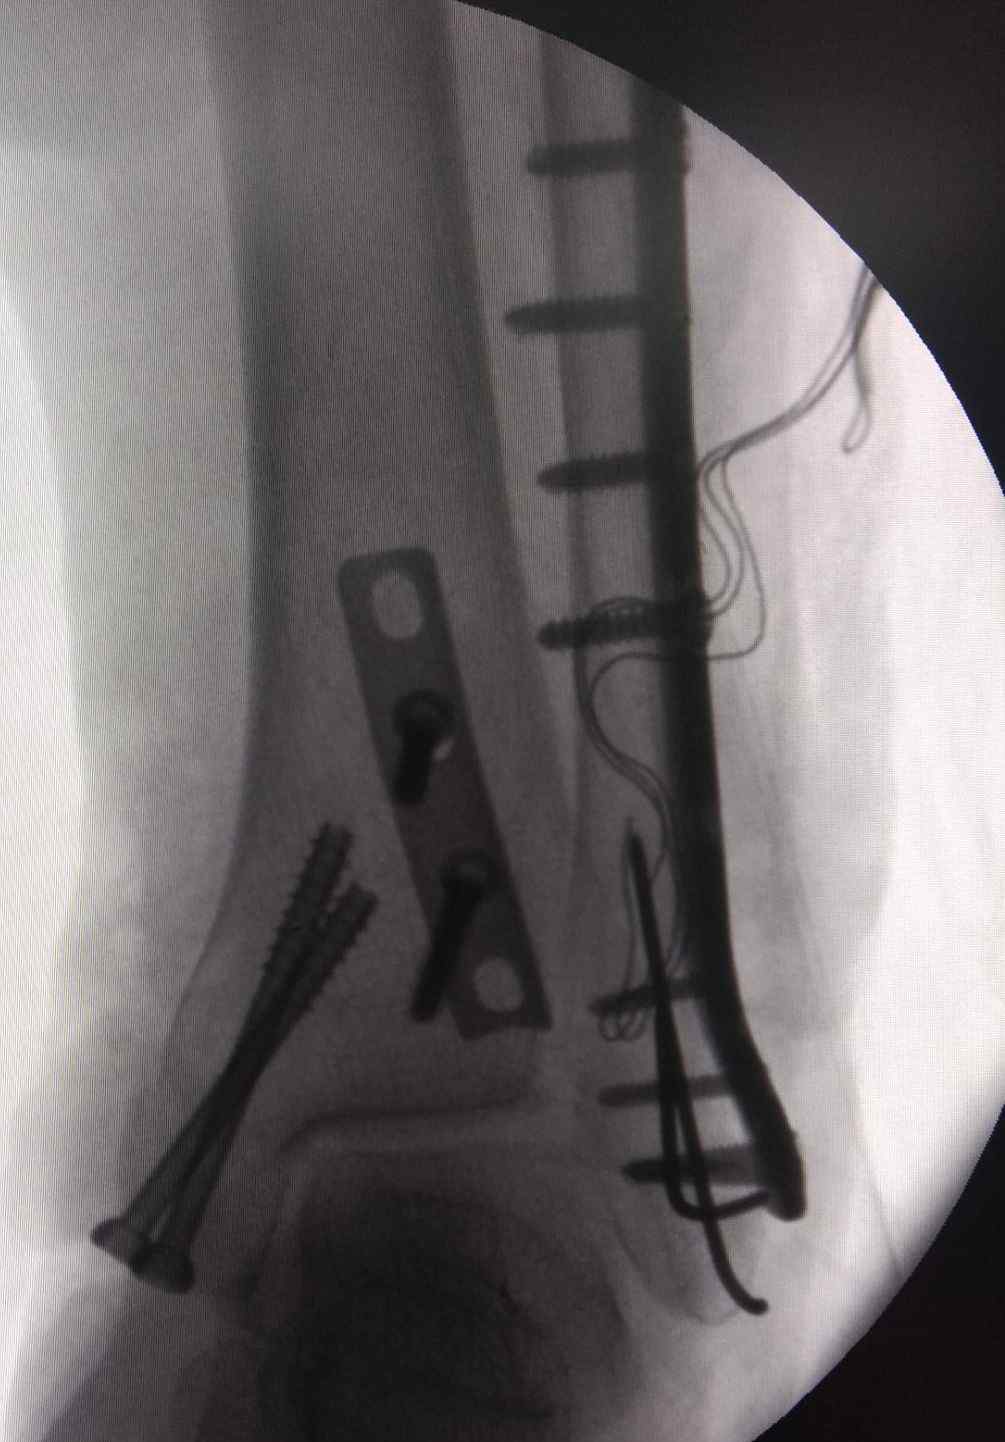

术后1月 病例二,李忍忍,男,31岁,左踝关节骨折,旋后外旋四度 病例三,患者,女,74岁,踝关节骨折,后内侧切口+外侧切口。